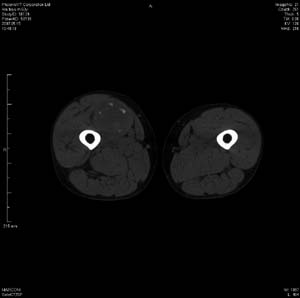

男 63岁 右大腿无痛性肿块11年,x片右大腿软组织肿块影,余无明显异常.ct值-13__239hu

右大腿股内侧股与收肌间隙间多发囊实性占位,界清.内示斑点状钙化.局部骨质无异常.肌肉推压移位表现.

考虑肌间隙病变.可有1,神经来源肿瘤.2,血管来源病变.3,淋巴来源肿瘤.4,脂肪来源肿瘤.5,滑膜来源肿瘤.结合病史只能考虑良性占位.建议增强或mri进一步分析.

同意,病史较长,病变周围分界清晰,考虑良性病变。病灶内有多发斑点状钙化,沿肌间隙生长,血管瘤或淋巴管瘤首先考虑。